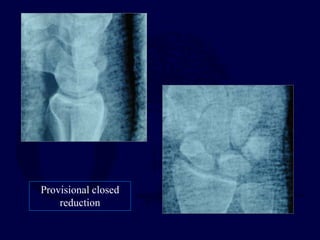

ORIF with volar and dorsal approaches

Procedure of Choice

Provisional closed

reduction